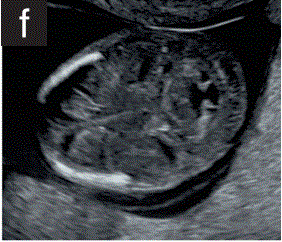

(3.6)头部下方的平面显示了两个丘脑和后颅窝区域,其中大脑脚和西尔维乌斯导水管、第四脑室和未来的大池为充液结构(图2f)。

胎儿mt是什么检查什么疼吗【文献学习/规范指南】ISUOG实践指南(2023更新): 11-14周胎儿超声检查(全文)_https://www.jmylbn.com_新闻资讯_第11张

图2 11+0至14+0周时,可作为详细胎儿超声检查的一部分获得的解剖图。

(f) 胎儿头部的横断后颅窝切面,显示丘脑、小脑、第四脑室、脑室导水管和大池。